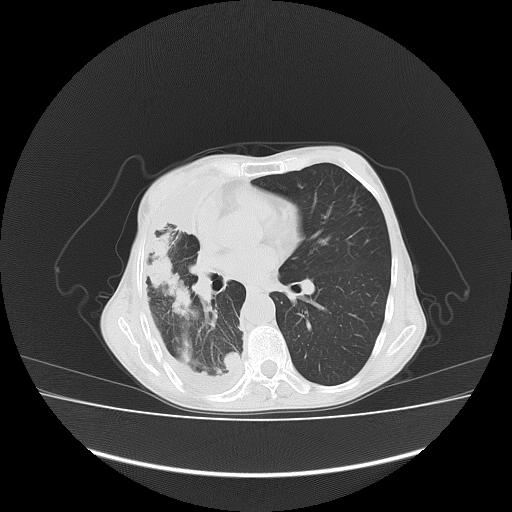

标题: CT16930:女 59 胸痛6个月 胸水脱落细胞学见瘤细胞 [打印本页]

标题: CT16930:女 59 胸痛6个月 胸水脱落细胞学见瘤细胞

可见多发肺内病灶,且胸膜病灶较多有圆球状而非丘状,多考虑胸膜转移瘤伴胸腔积液,右侧胸廓缩小固定,且部分病灶呈丘状,尚不除外恶性胸膜间皮瘤伴肺内转移

右侧胸膜增厚,局部呈结节状增厚,右侧胸腔少量积液。双肺未见确切肿块影。纵隔未见淋巴结肿大。气管、支气管通畅。考虑右侧胸膜间皮瘤(恶性?)可能性大。不除外癌性胸膜炎。

恶性胸膜间皮瘤伴肺内转移可能性大;或胸膜、肺内均为转移瘤,左肺下叶亦见多发小结节影。

右侧胸廓塌陷,右侧胸膜广泛增厚并见多发胸膜结节,右侧少量胸腔积液并包裹。

右侧广泛胸膜增厚,局部呈结节状增厚,右侧胸腔少量积液。双肺未见确切肿块影。纵隔未见淋巴结肿大。气管、支气管通畅。考虑右侧胸膜间皮瘤(恶性?)可能性大。支持!

右侧胸膜转移瘤,原发灶可能就在在右肺,另外建议检查右侧乳腺.

右胸腔结节均考虑来自胸膜(部分来源于叶裂),考虑胸膜间皮瘤或转移瘤.